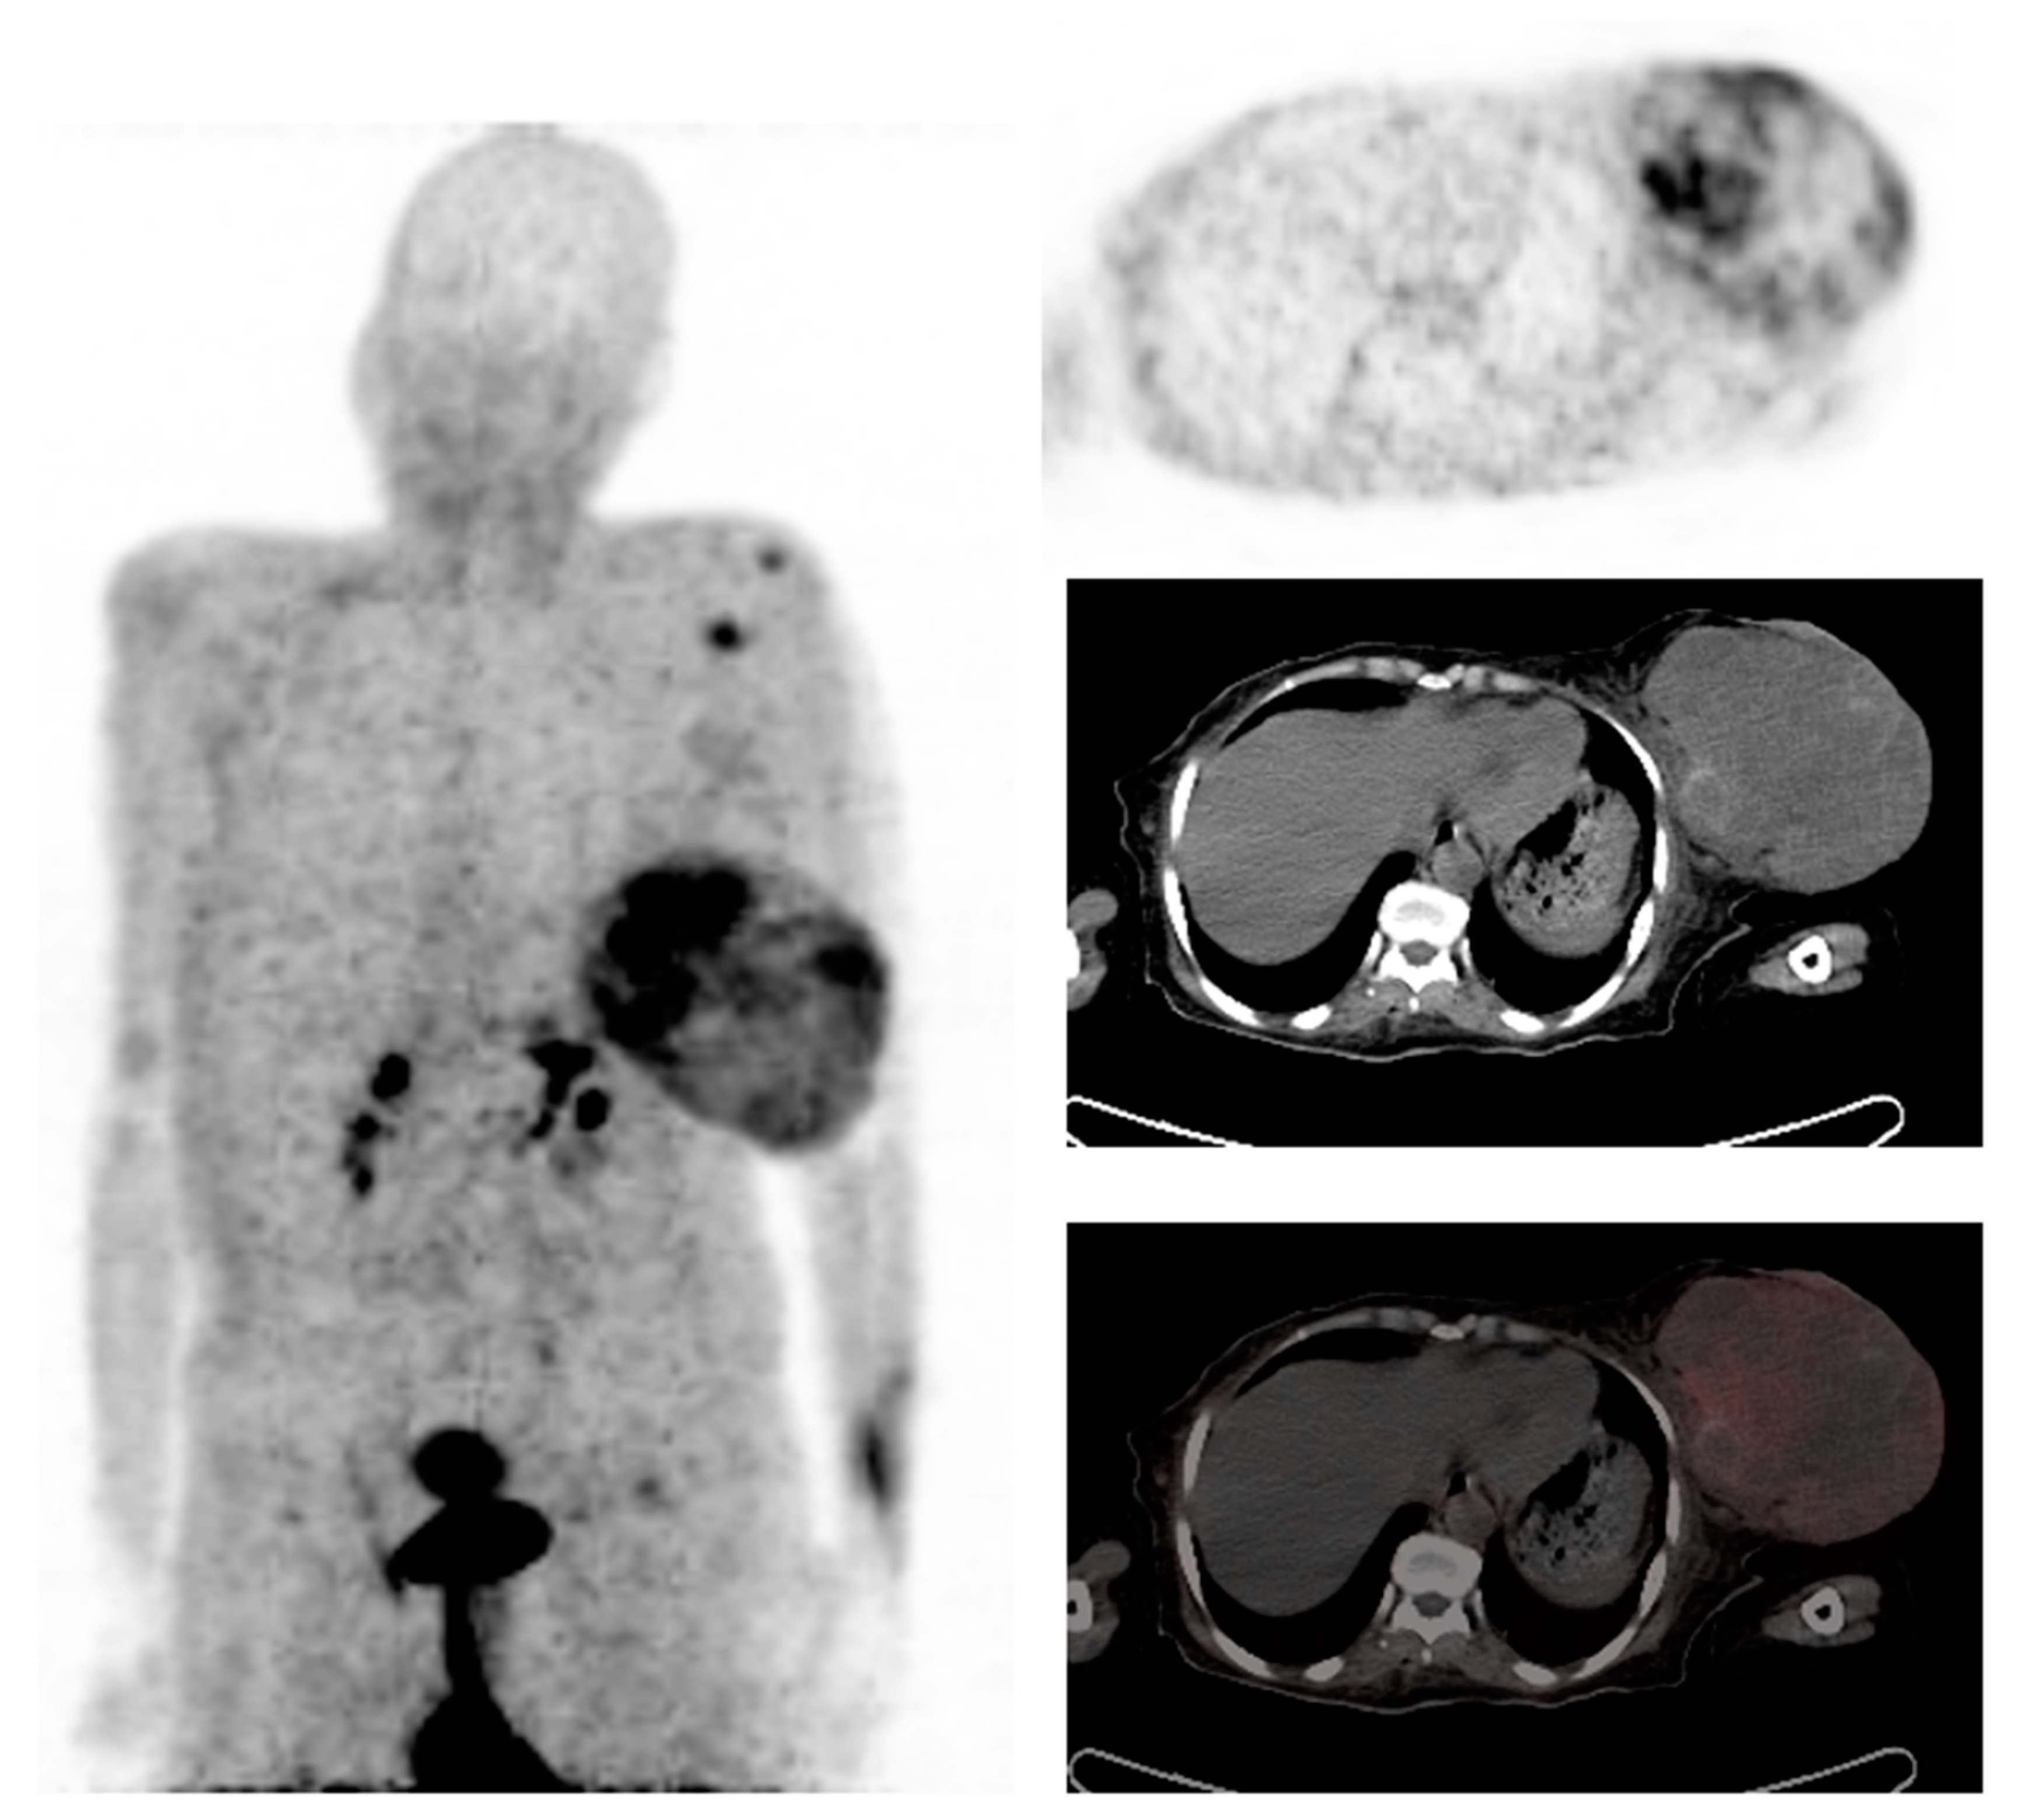

- Komek, H.; Can, C.; Guzel, Y.; Oruc, Z.; Gundogan, C.; Yildirim, O.A.; Kaplan, I.; Erdur, E.; Yildirim, M.S.; Cakabay, B. (68)Ga-FAPI-04 PET/CT, a new step in breast cancer imaging: A comparative pilot study with the (18)F-FDG PET/CT. Ann. Nucl. Med. 2021, 35, 744–752. [Google Scholar] [CrossRef]

- Elboga, U.; Sahin, E.; Kus, T.; Cayirli, Y.; Aktas, G.; Uzun, E.; Cinkir, H.; Teker, F.; Sever, O.; Alper, A.; et al. Superiority of 68Ga-FAPI PET/CT scan in detecting additional lesions compared to 18FDG PET/CT scan in breast cancer. Ann. Nucl. Med. 2021, 35, 1321–1331. [Google Scholar] [CrossRef]